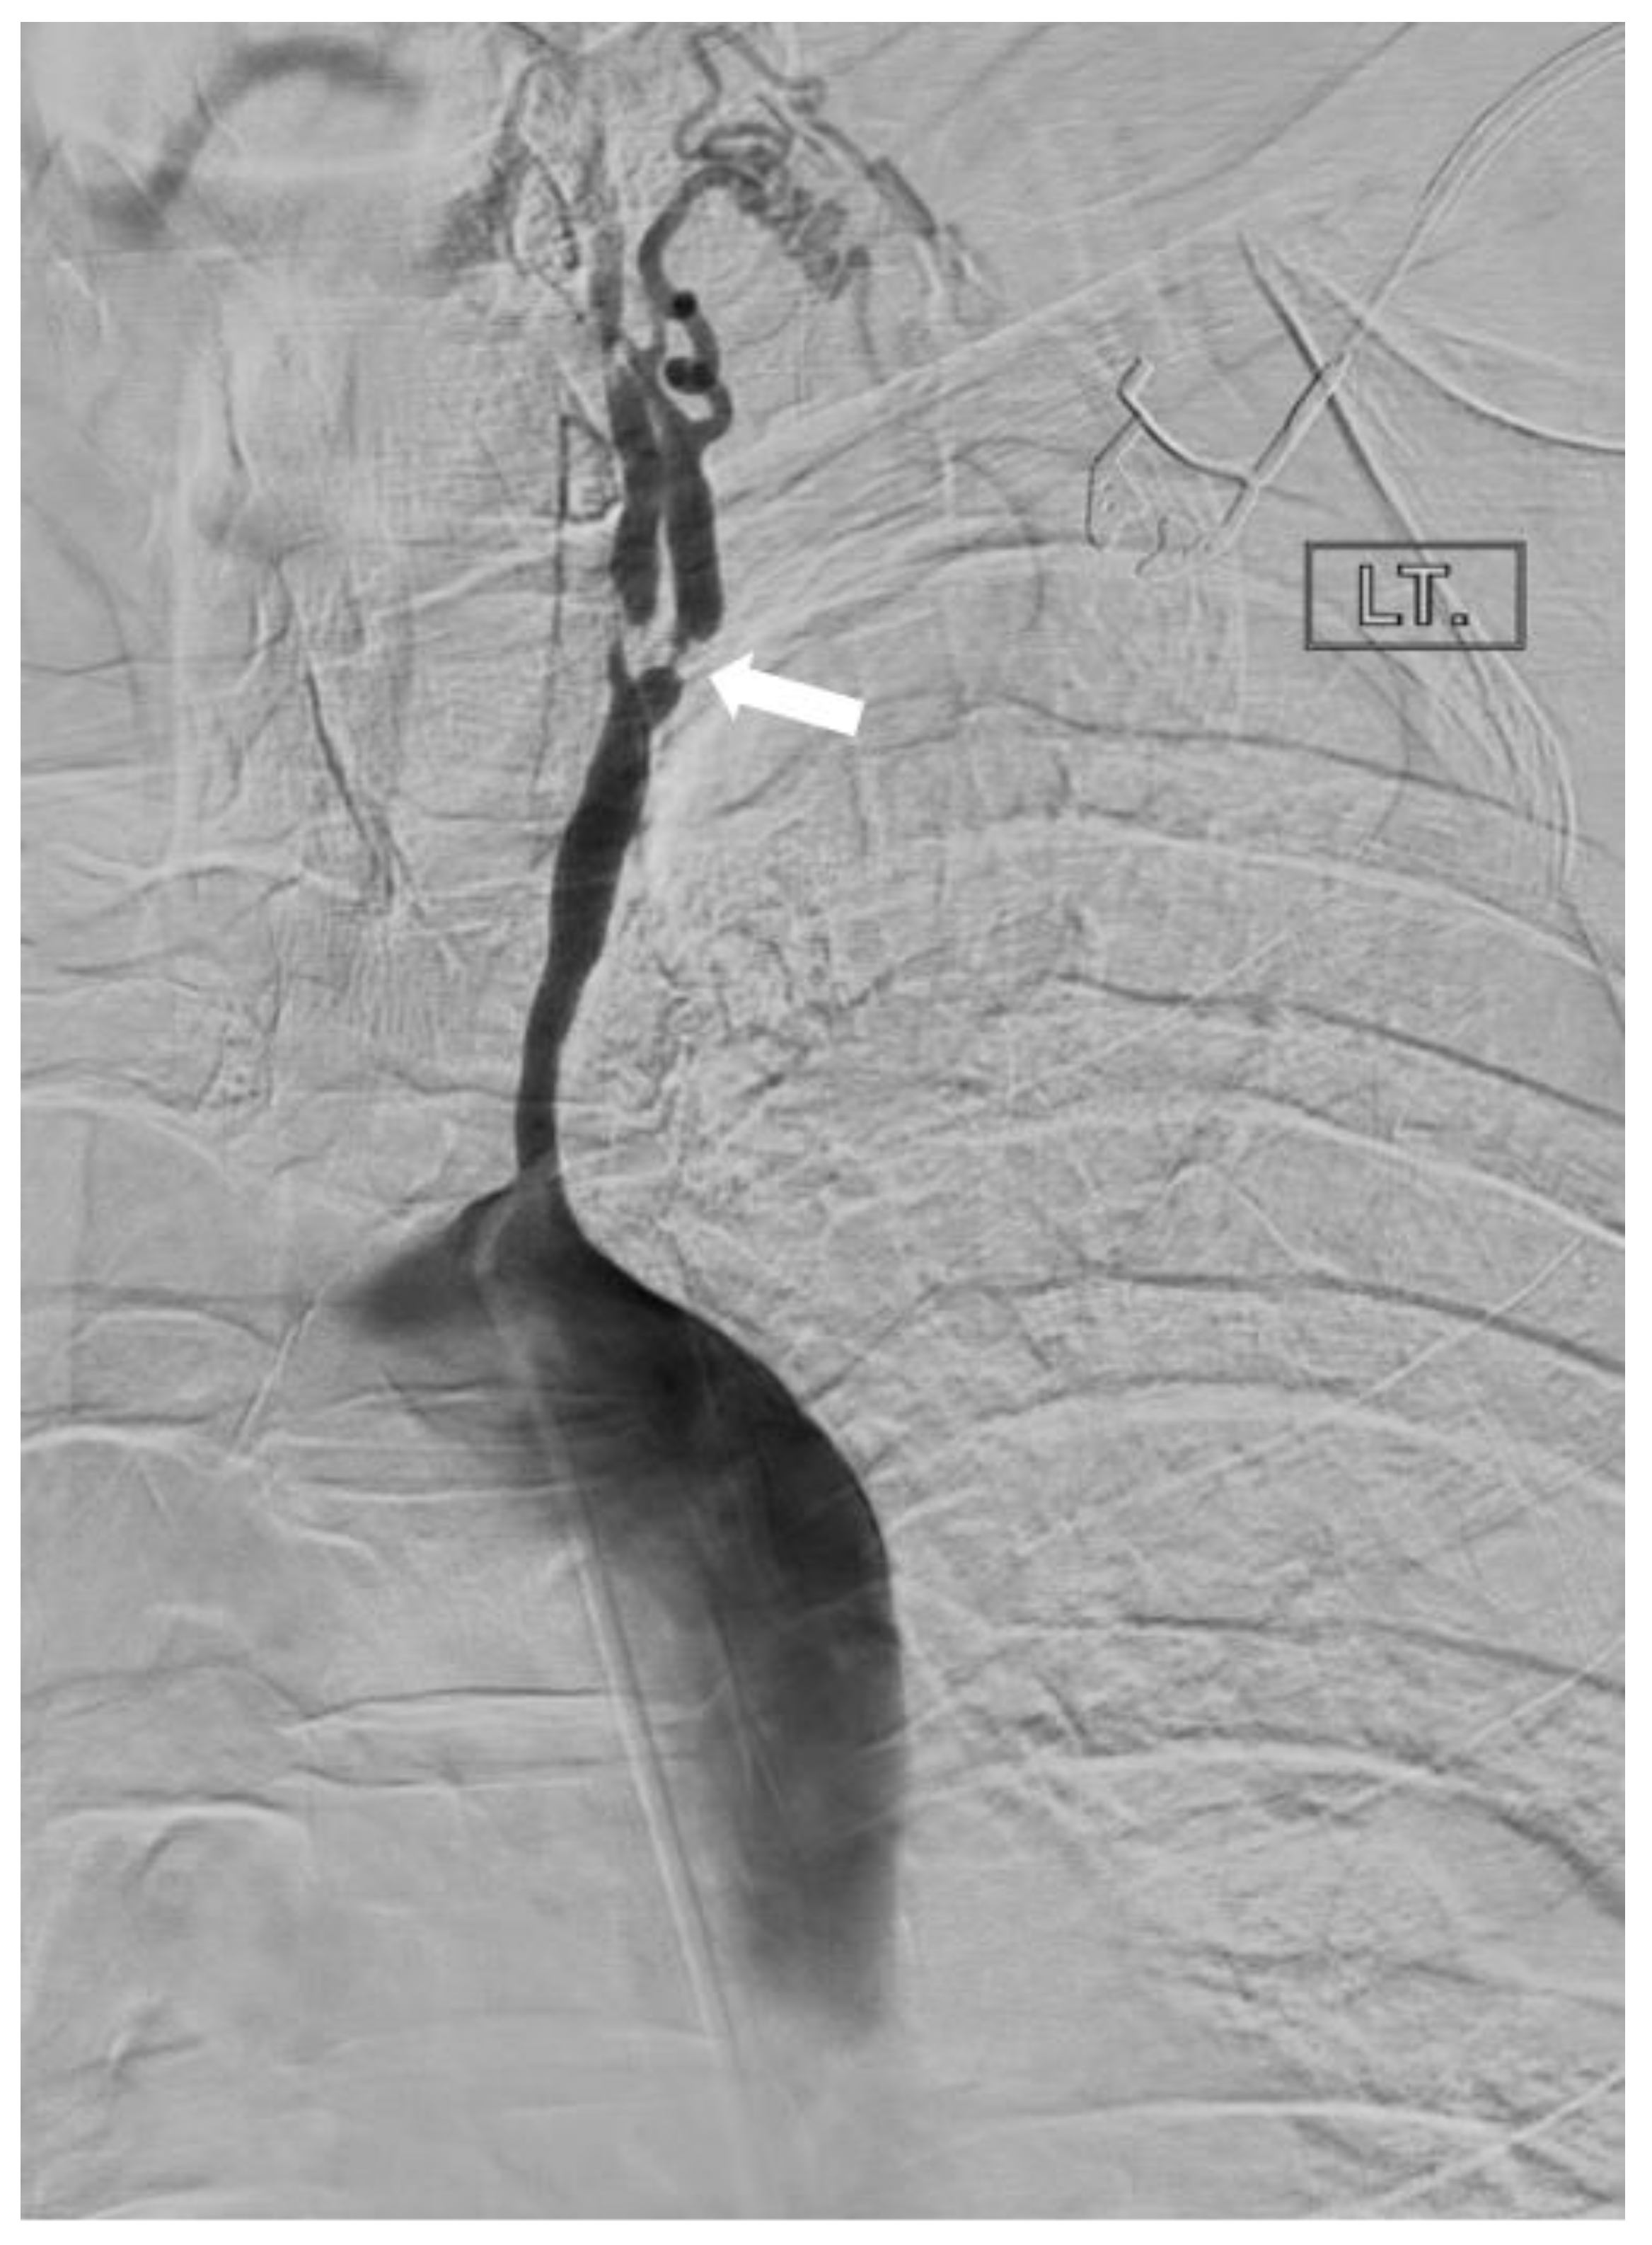

2.1.2. Takayasu’s Arteritis

- Ghembaza, M.E.A.; Boulenouar, F.; Lounici, A. “Macaroni Sign” in Takayasu Arteritis. J. Cardiovasc. Imaging 2018, 26, 186–187. [Google Scholar] [CrossRef]

- Barra, L.; Kanji, T.; Malette, J.; Pagnoux, C. Imaging modalities for the diagnosis and disease activity assessment of Takayasu’s arteritis: A systematic review and meta-analysis. Autoimmun. Rev. 2018, 17, 175–187. [Google Scholar] [CrossRef] [PubMed]